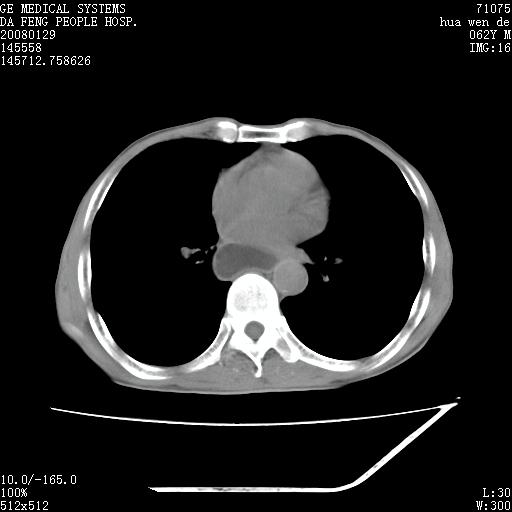

男性,67岁。作肺部检查时发现

理由:1、右上肺内病灶,空洞形成,有液平。

2、肺内多处炎症。

3、前段肺内炎症,支气管引流通畅,与肿块无关系。

1.整个食管扩张,未见明显占位性病变,贲门区亦未见明显占位病变,考虑:贲门失驰缓症;

2.右上肺病变边缘可见毛刺,囊壁厚度不均匀,周围境界较清楚,未见炎性渗出性影,右上肺外带可见片状影,边缘不清,考虑:肺癌伴空洞形成、右上肺炎。

食管全程扩张,壁均匀不厚,喷门失弛缓症

右上肺空洞可见液平,临近肺野磨玻璃密度,考虑1.结核2.脓肿